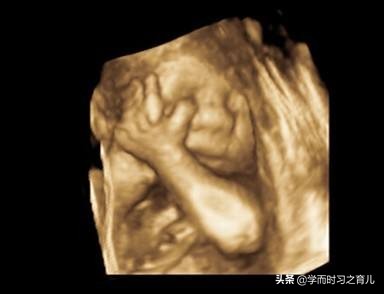

其实一般在怀孕22~26周,医生会安排准妈妈进行胎儿大排畸检查,主要通过三维或者四维彩超(两者选择其中一个即可)进行,可以说这是整个孕期最重要的检查项目之一。

虽然四维彩超已经是目前最先进的技术了,不仅可以检查胎儿的发育情况,还可以实时看到胎宝宝的各种动作,但这还是无法检查出胎儿所有的畸形,存在一定的局限性。